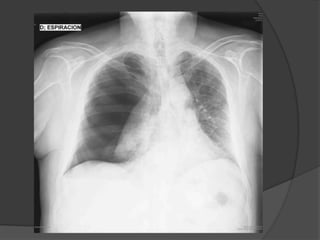

La radiografía simple del tórax es confirmatoria. En

casos de neumotórax pequeños, una radiografía

tomada en espiración realza el neumotórax.